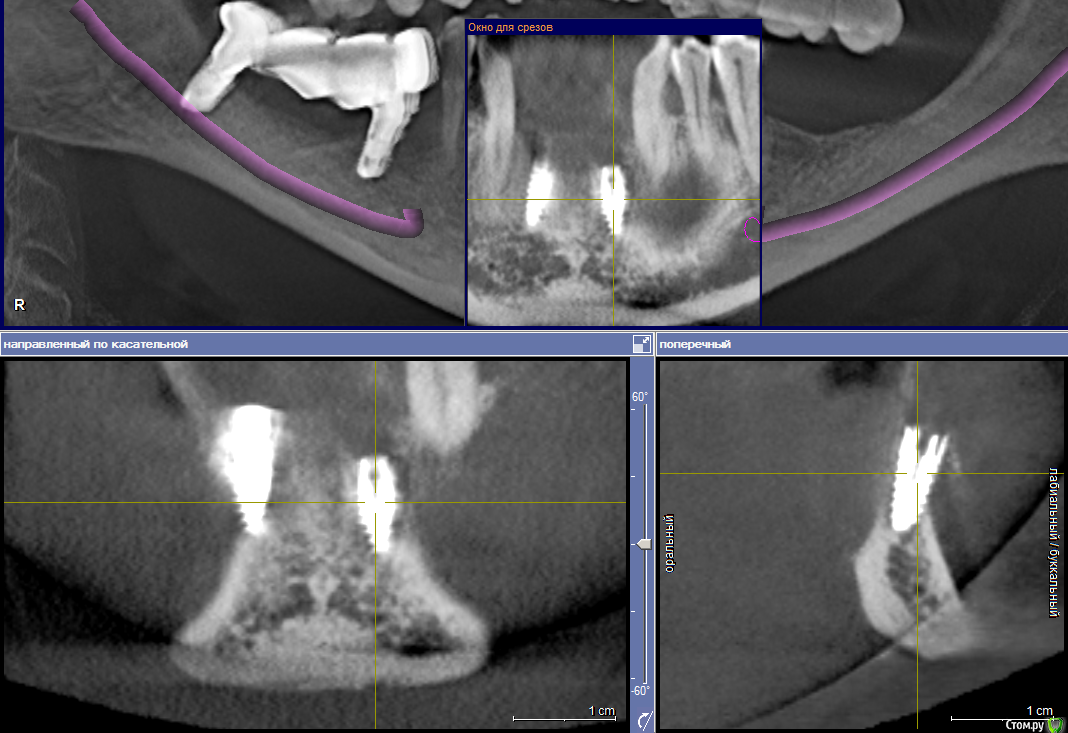

samanta66 Опубликовано 22 марта, 2015 Поделиться Опубликовано 22 марта, 2015 Добрый день.Срочно нужна консультация специалистов. Импланты (передние) поставлены более 9 месяцев назад. Казалось, вросли основательно. На этапе протезирования, когда уже полностью был готов протез, ортопед сказал, что имплант расшатался, послал к хирургу. Сделали снимок, на котором увидели, что имплант стоит не вертикально (как было изначально). 1. Как-то можно исправлять ситуацию? Хирург предлагает убирать этот имплант и через время ставить новый. У меня сомнения: не повторится ли ситуация ?2. Почему имплант расшатался? Во время многочисленных примерок ортопед прилагал немалые усилия, так как что-то там не влезало по моим ощущениям. Можно свидетельствовать, что ортопед своими действиями "свернул" имплант ? Он отказывается переделывать бесплатно свою работу. Для сравнения предлагаю 2 КТ (за октябрь и март). октябрь март крупнее Ссылка на комментарий

diesel87 Опубликовано 22 марта, 2015 Поделиться Опубликовано 22 марта, 2015 стоит судя кт он так же как его и ставили. только видимо нет кости вестибулярно. скорее всего перестановка Ссылка на комментарий